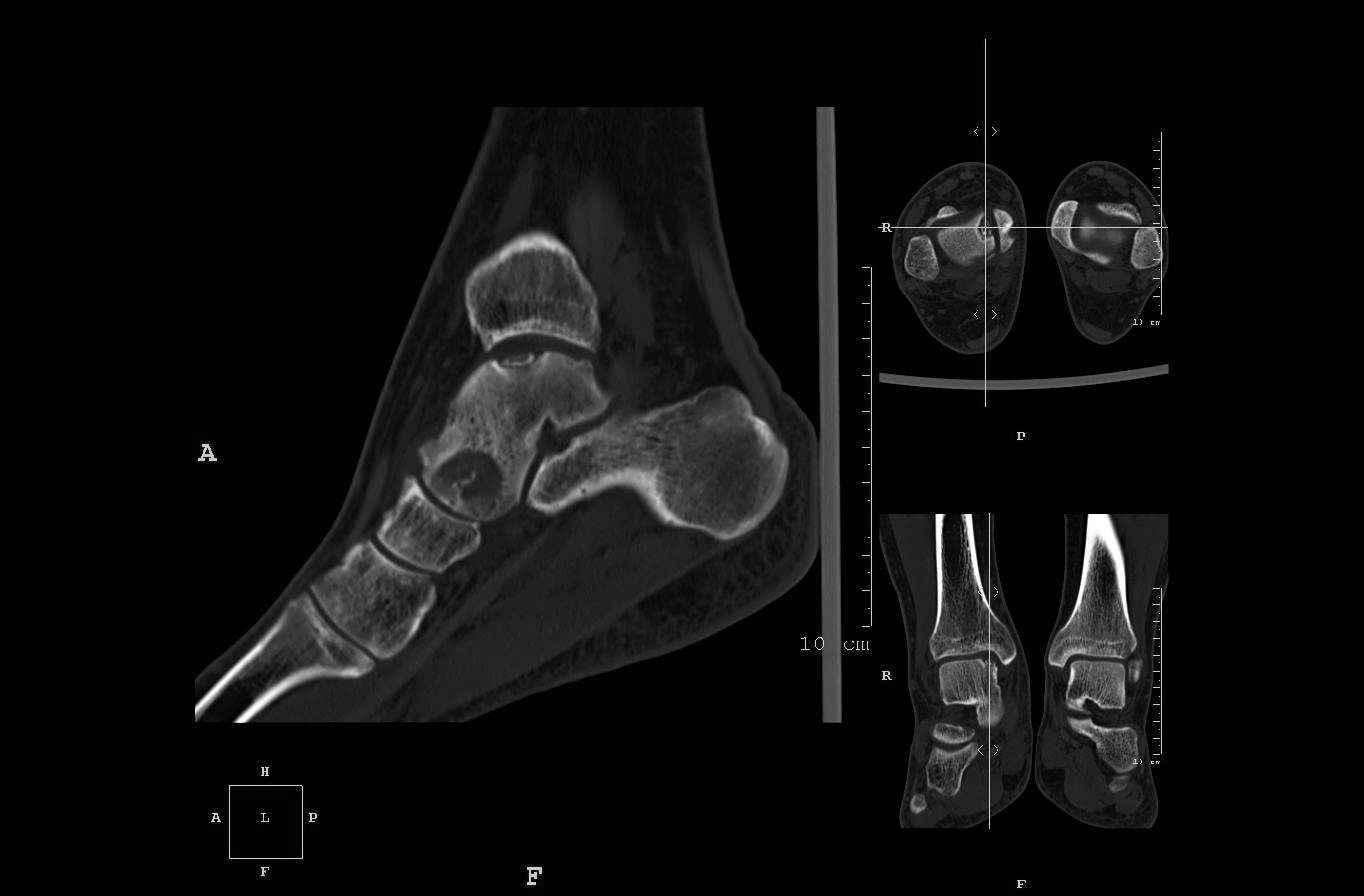

Уважаемые коллеги, обратился за помощью пациент, мужчина, 25 лет. С жалобами на болевой

синдром в области голеностопного сустава и среднем отделе стопы. Травму отрицает. Со слов,

болевой синдром в течении 1 года. Последние 1-1.5 мес периодически вынужден пользоваться

костылями. После ограничения нагрузки боли уменьшаются. Соматически здоров. До появления

болей активно занимался рукопашным боем.

На СКТ картина рассекающего остеохондрита блока

таранной кости, киста шейки таранной кости с признаками импрессии суставной поверхности. А

также - разрастания переднего края б\берцовой кости сопровождающиеся клиникой импиджмент

синдрома.